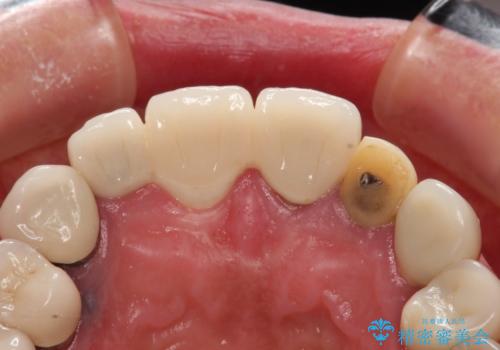

- 治療途中で装着していた仮歯汚れてしまい、恥ずかしいとのことで来院された患者様です。

土台の金属色が透けて見えてしまうため、ファイバーコアに置き換えた上で、オールセラミッククラウンにて補綴することとしました。